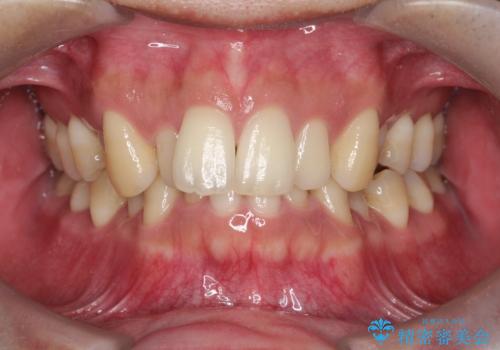

前歯のデコボコと深い咬み合わせを解消

- 前歯のデコボコ(叢生)と、上下の歯の重なりが深い「ディープバイト(過蓋咬合)」を主訴にご来院されました。精密検査の結果、歯が並ぶスペースが不足しているため、上顎左右の小臼歯を抜歯することでスペースを確保し、全体の咬み合わせを改善する治療計画を立案しました。これにより、見た目の改善だけでなく、過度な咬み合わせによって生じる歯や顎への負担も軽減することを目指します。

今回の矯正治療では、まず歯が並ぶスペースを確保するため、上顎の小臼歯を抜歯しました。抜歯によってできたスペースを利用して前歯を奥へ移動させ、デコボコを解消。同時に、奥歯の咬み合わせを調整することで、深すぎた咬み合わせであるディープバイトも改善しました。治療の結果、長年気にされていた前歯のデコボコが解消され、理想的な歯並びに。さらに、正しい咬み合わせを獲得したことで、機能的にも安定した美しい口元になりました。